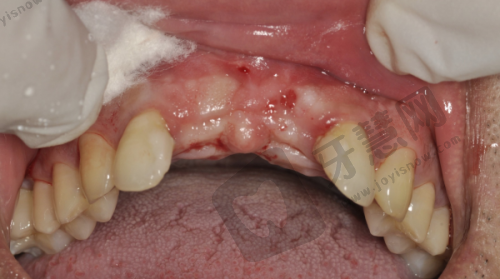

1. 全方面口腔诊疗服务:从儿童的修牙、涂氟、窝沟封闭到正畸筛查等项目都能提供,满足不同年龄段患者的口腔需求。

2. 精良检查技术:采用拍片和口扫技术,360度扫描面部,能逐颗检查牙齿,为正确诊断提供有力支持。

3. 清晰诊疗流程:精良行面诊,再通过各种检查手段全方面了解患者口腔状况,制定个性化的治疗方案,让患者体验效率高、专精的服务。